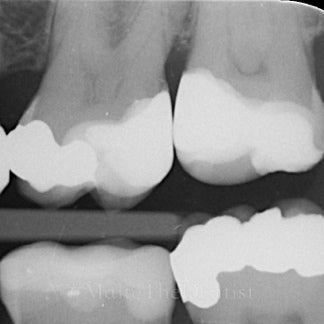

• Tørre, stabile arbejdsforhold og kofferdam, der faktisk fungerer

• Forudsigelige matricer og stramme kontaktpunkter

• Et enkelt, reproducerbart bonding-setup

• Carieseksavering med omtanke

• Form, anatomi og workflow, der gør dine fyldninger hurtigere og bedre